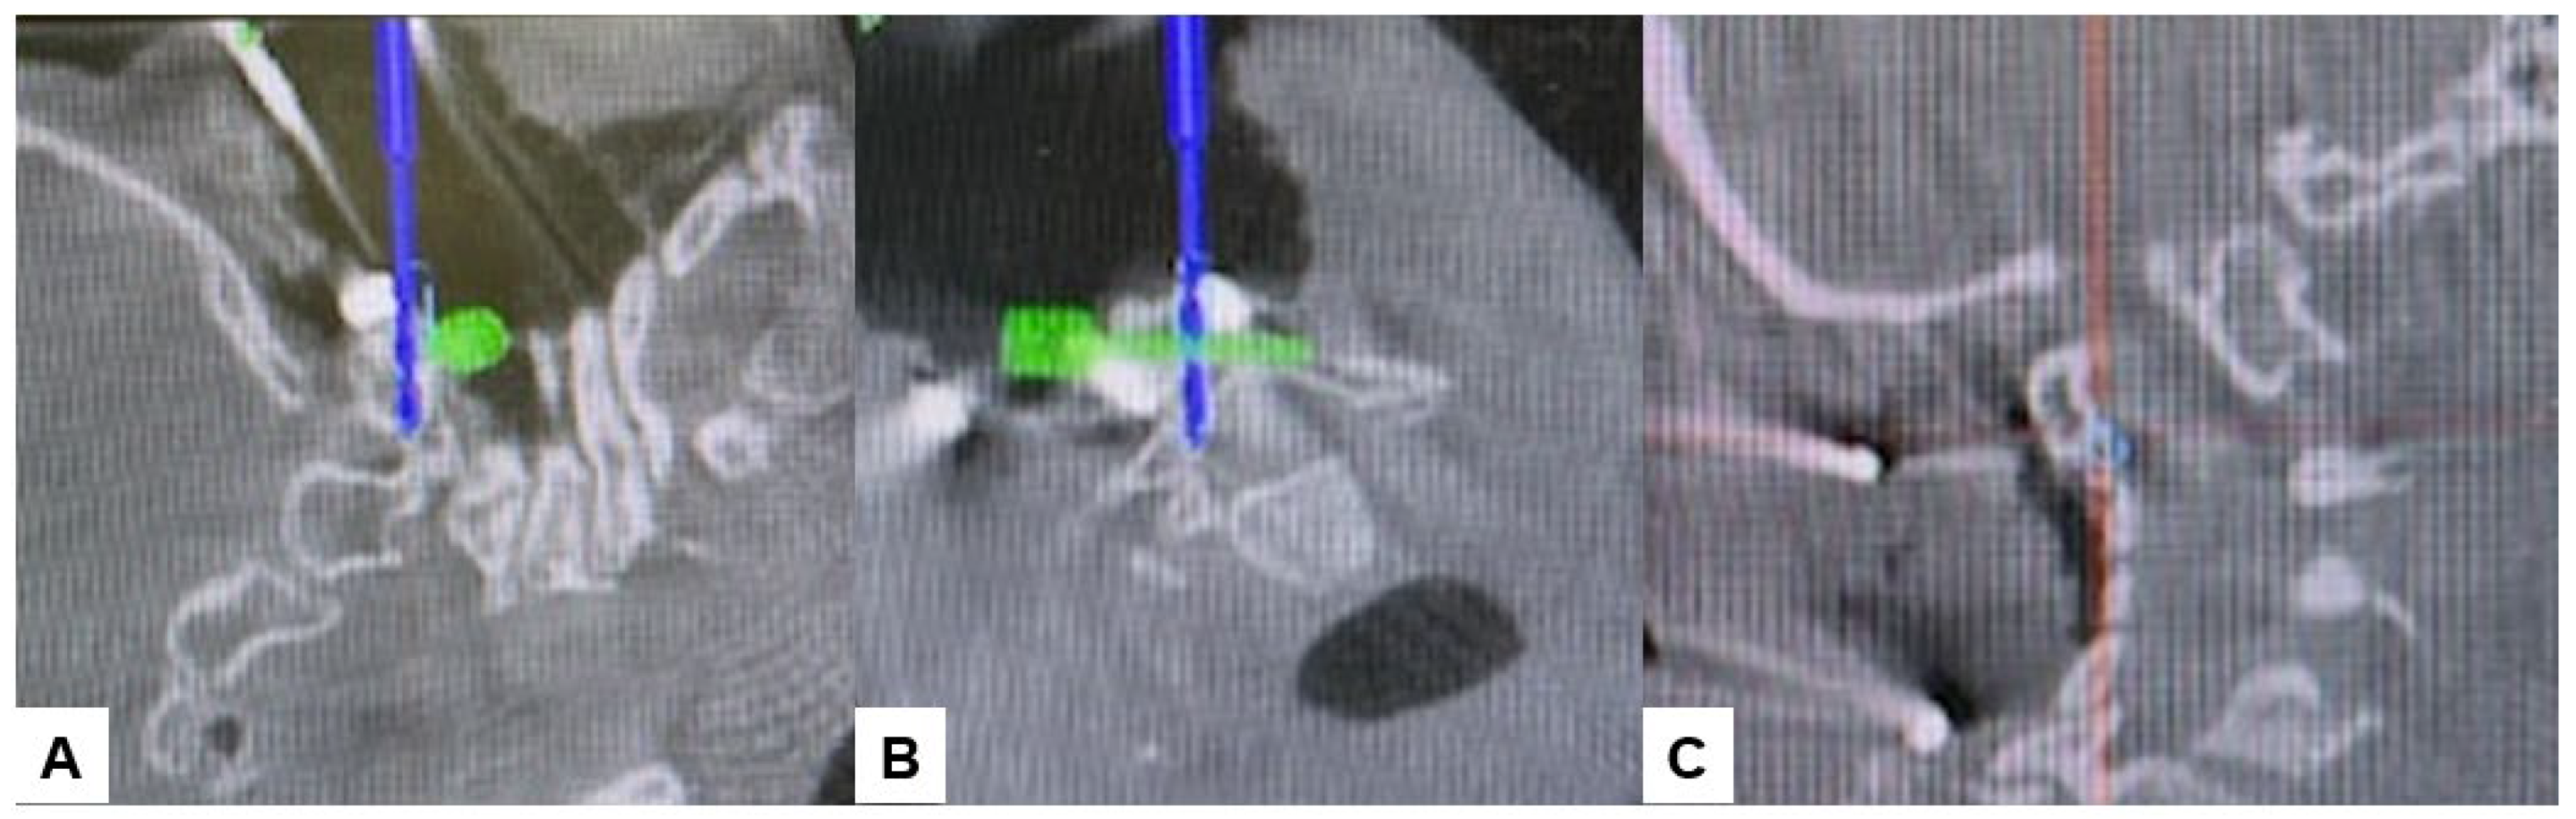

Then, under navigation guidance, the thickest portion for occiput screws was identified, and a total of 6 occipital screws were inserted using a navigated high-speed burr and pointer (Figure 9). The Mayfield skull clamp was loosened and the skull was rotated forward, with traction under neuromonitoring (Figure 10 and Figure 11). Finally, two cobalt–chrome rods were connected to the screw head and more distraction was performed with screw distraction for adequate reduction (Figure 12).

Figure 9.

Occipital screwing, (A) sagittal view, (B) Axial view, (C) 3D view. The adequate screw point is indicated by the navigated pointer.

Positioning occipital screws in occipitocervical instability poses a significant challenge, particularly to precision. It is crucial to accurately identify the thickest part of the lower occiput to safely insert the screws without risking injury to surrounding anatomical structures or the dura, which could lead to cerebrospinal fluid (CSF) leakage (Figure 7). Successful placement of occipital screws necessitates a thorough understanding of bone anatomy and its relationship with neurovascular structures, the spinal canal, hypoglossal canal, vertebral arteries, and the jugular foramen [44]. Using our technique, utilizing a navigation-mapped high-speed burr and probe, we achieved precise insertion of occipital screws with optimal length by directly visualizing and identifying the thickest part of the occiput. This approach, guided by navigation, ensures high accuracy and enhances screw purchase and strength.